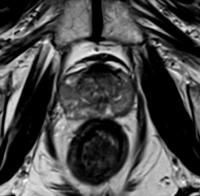

前立腺